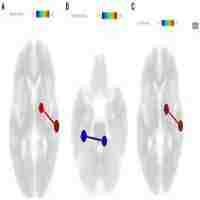

P.325 Reward anticipation processing in major depressive disorder and prediction of treatment response - a functional magnetic resonance imaging study